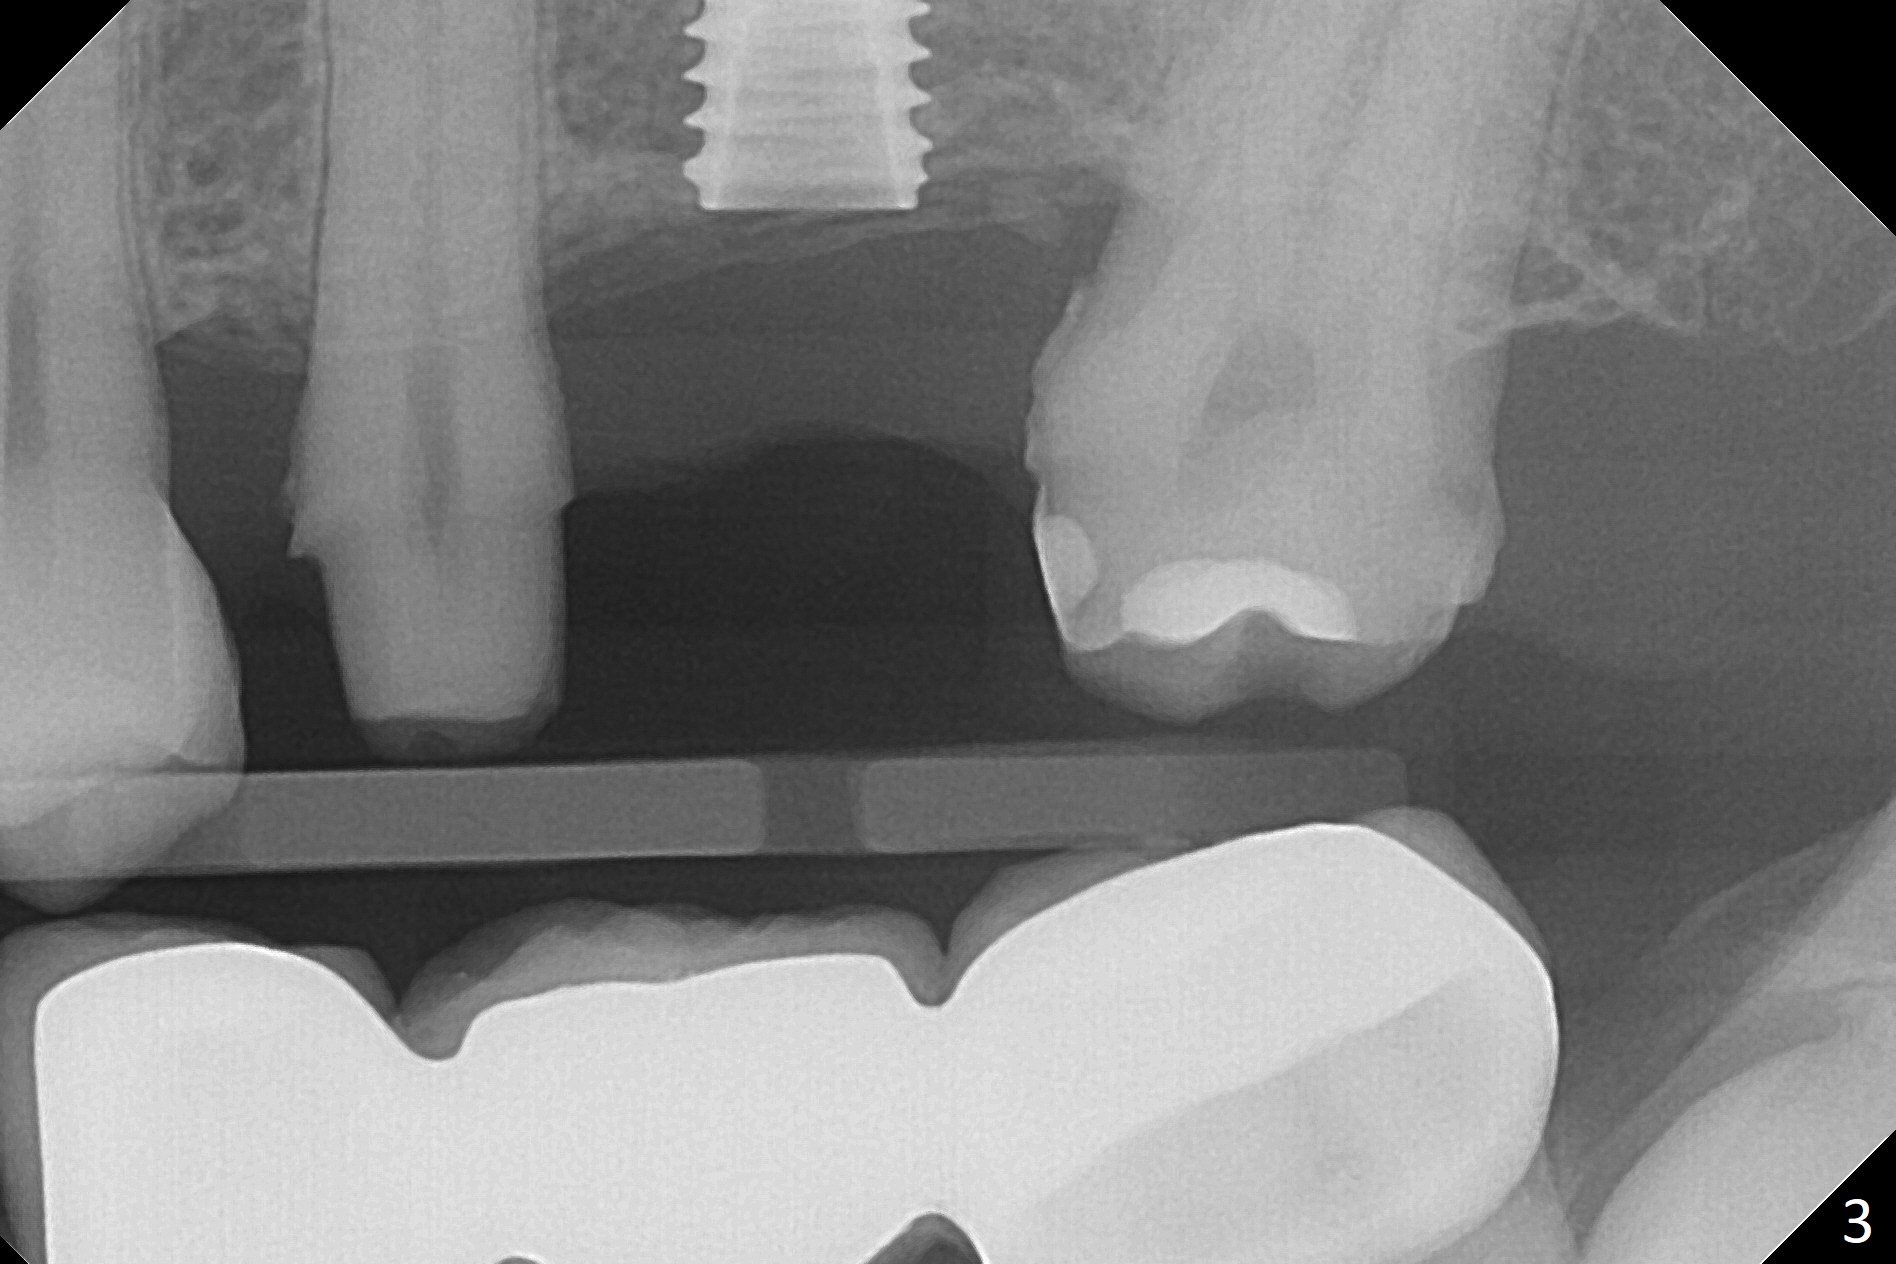

#13-15 FPD has not been used properly because of discomfort for 2 years. Before its removal, the discomfort derives from probing of the distal of #13 and mesial of #15, corresponding to calculus in the proximal areas. SRP is performed in UL quadrant after FPD removal. Bone density at the crest of the edentulous area is normal, while that of the medulla is low. After determination of trajectory and depth of initial osteotomy (Fig.1 (5 mm straight incision)), the site is underprep for a 4.5x13 mm Implant. Following adjustment, the implant is placed slightly subcrestal (Fig.2,3). It is possible that the discomfort of the previous FPD is due to overload, as suggested by the prominent buccal plate at #13 and 15, as compared to that of #12 (Fig.4 (5.2x4.5(3) mm cementation abutment at #14). Postop follow up shows that the tooth #15 may need RCT. The implant seems to enter the sinus (Fig.5 (2.5 months postop)) and be ready for restoration 3.5 months postop (Fig.6).